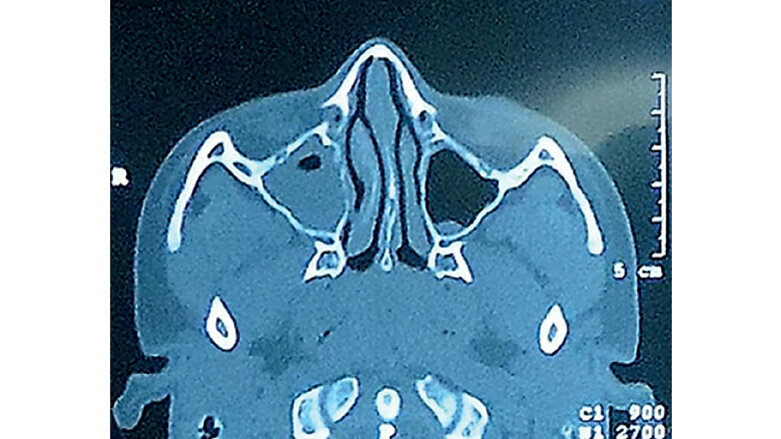

Figura 3. Displasia fibrosa vista por TC. (Colaboración: Dr. ORL. Vinicio Toscano)

Displasia fibrosa: invasión de hueso por tejido fibro-óseo con capacidad de expansión. Clínicamente se observa deformidad facial ósea, obstrucción nasal progresiva, disminución de agudeza nasal.